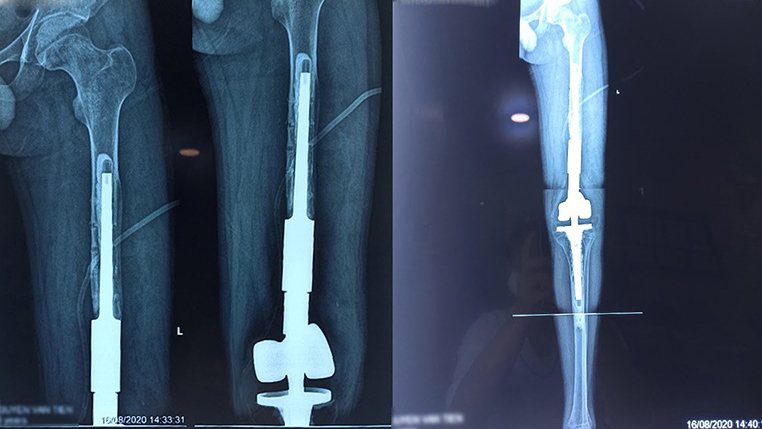

Thay xương đùi toàn phần là một thủ thuật phẫu thuật cứu sống những bệnh nhân bị tổn thương nghiêm trọng hoặc mắc bệnh ảnh hưởng đến toàn bộ xương đùi. Xương đùi bị tổn thương được thay thế bằng xương nhân tạo và các khớp giả được sử dụng để thay thế hông và đầu gối. Phương pháp này chỉ được sử dụng khi các phương pháp điều trị khác không hiệu quả và tình trạng của xương đùi rất nghiêm trọng.

Thay xương đùi toàn phần là một phẫu thuật chuyên môn cao liên quan đến việc thay thế toàn bộ xương đùi của bệnh nhân - xương dài nhất trong cơ thể. Thủ thuật này cũng bao gồm việc thay thế đồng thời cả khớp hông và khớp gối bằng các thành phần nhân tạo. Lần đầu tiên được thực hiện vào năm 1952 bởi Buchman, phẫu thuật thay xương đùi toàn phần cho đến nay vẫn là ca phẫu thuật hiếm và phức tạp, chủ yếu được thực hiện tại các trung tâm y tế tiên tiến trên toàn thế giới.

Thay xương đùi toàn bộ là một can thiệp phẫu thuật lớn với các chỉ định cụ thể, thường là đối với các tình trạng đe dọa tính mạng hoặc tàn tật nghiêm trọng. Xương đùi nhân tạo được làm bằng vật liệu bền, thường là kim loại hoặc vật liệu tổng hợp chuyên dụng cấp y tế, được thiết kế để phục hồi chức năng và khả năng vận động của chân, đồng thời có tác dụng giảm đau. Vì thủ thuật này rất phức tạp và đầy thử thách nên thường dành cho những bệnh nhân có ít hoặc không có lựa chọn thay thế nào khác.

Bước thứ hai bao gồm lập kế hoạch trước phẫu thuật chi tiết. Các phép đo chính xác của xương đùi là điều cần thiết để đảm bảo xương đùi nhân tạo được thiết kế phù hợp với giải phẫu của bệnh nhân. Bác sĩ phẫu thuật sẽ sử dụng công nghệ 3D để đo chiều dài, đường kính đầu và trục giải phẫu của xương đùi. Nếu giải phẫu của xương đùi tổn thương bị thay đổi, các phép đo từ chân khỏe mạnh đối diện sẽ được sử dụng để hướng dẫn thiết kế.

Với dữ liệu này, xương đùi nhân tạo tùy chỉnh được tạo ra bằng công nghệ in 3D tiên tiến. Bước này rất quan trọng để đạt được sự vừa vặn hoàn hảo, đây là chìa khóa cho kết quả thành công lâu dài.

Sau khi cắt bỏ xương đùi bị tổn thương, các mô mềm xung quanh được sinh thiết để kiểm tra các tế bào ác tính. Nếu không phát hiện thấy ác tính, bác sĩ phẫu thuật sẽ tiến hành cấy ghép xương đùi nhân tạo, định vị chính xác trong giải phẫu của bệnh nhân. Sau khi xương đùi đã vào đúng vị trí, khớp hông và khớp gối sẽ được tái tạo để phục hồi chức năng hoàn toàn.

Bước tiếp theo bao gồm việc khâu cẩn thận các gân và cơ tại các điểm bám của chúng vào xương đùi nhân tạo. Bác sĩ phẫu thuật kiểm tra kỹ lưỡng độ ổn định của khớp gối và khớp hông và đánh giá lại vị trí của xương đùi theo định dạng 3D để đảm bảo mọi thứ được căn chỉnh đúng cách.